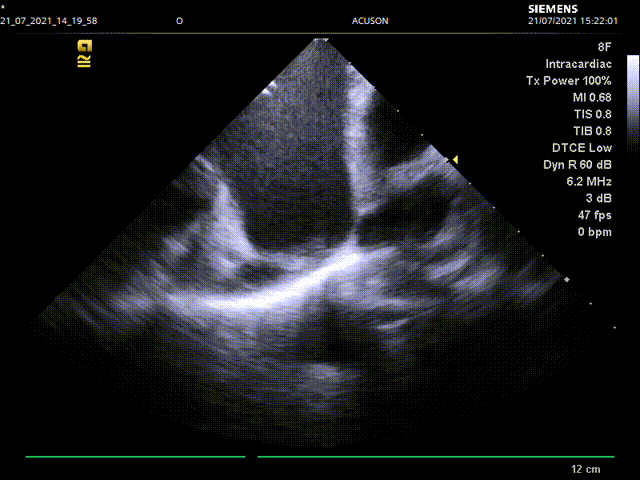

手术主要流程:经右股静脉入路,通过房间隔穿刺,将8F ICE导管送入左心房,在左心房通过三个不同的位置和角度测量左心耳锚定区大小和深度:左上肺静脉脊部角度、右肺静脉角度,二尖瓣环角度。而后进行左心耳造影,多种方式测量左心耳大小,选择合适病人情况的封堵器。放置左心耳封堵器后再用同样位置角度评估封堵情况。

心腔内超声左房内二尖瓣水平测量左心耳开口锚定区和深度

心腔内超声左房内二尖瓣水平评估封堵情况